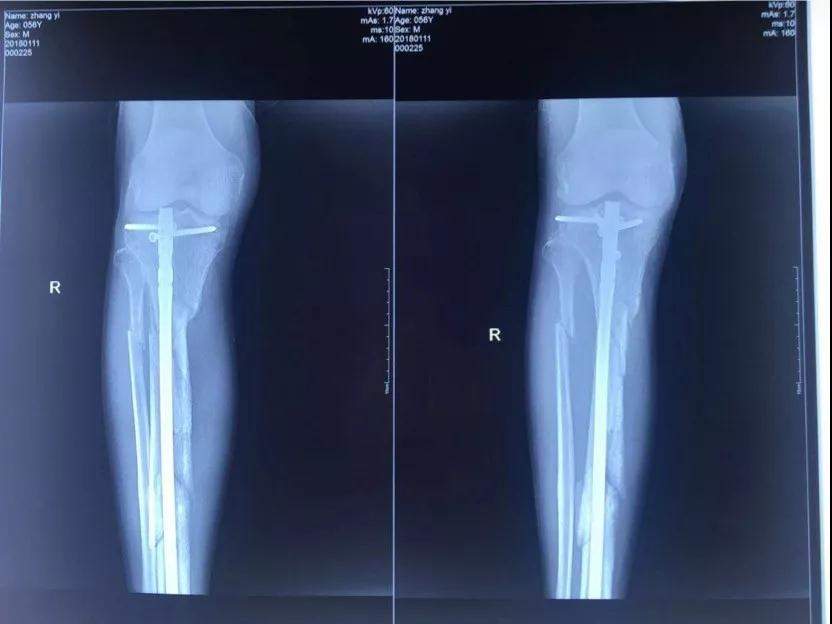

2017年10月18日十九大召開的當天下午五點多鐘,我像往常一樣去師範學院院裏老人居住的地方吃晚飯,此時,早已等待在老人樓下的一輛無牌照車裏出來四個蒙面人將我的腿打斷後逃走,這是十九大召開的的當日,是光天化日之下在大學的校園裏,是當着校園裏的教職工的面有預謀有組織的謀害。住院手術之後該團伙依然繼續到新院區繼續騷擾威脅,楊XX指使醫院會計在未履行任何財務手續的情況下從城南醫院挪用現金一千一百萬元,從兒媳婦XX也屬於城南醫院個人卡河北農信尾號XXXX中轉走五百萬元,此情況已經向安次區刑警隊和廊坊市公安局趙進晉局長報案’,至今至我傷殘和挪用醫院資金幕後指使依然逍遙法外。

2017年10月18日,張院長在廊坊師範學院院內遭受4名歹徒毆打至右腿粉碎性骨折,4名歹徒和背後指使者趙XX 均已落案。